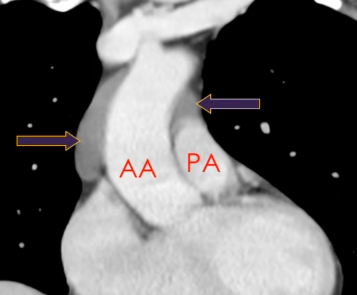

Récessus Aortique supérieur

Sinus Transverse